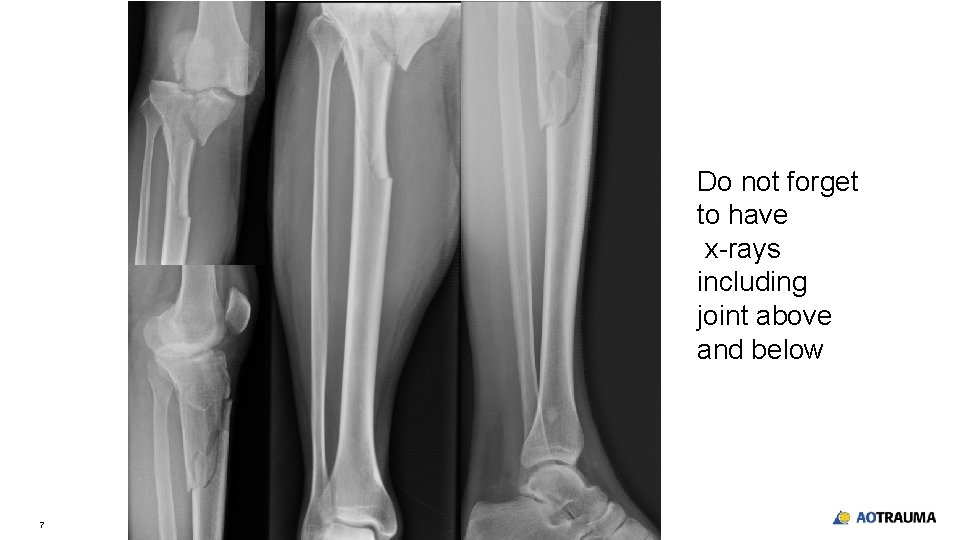

Do not forget to have x-rays including joint above and below 7